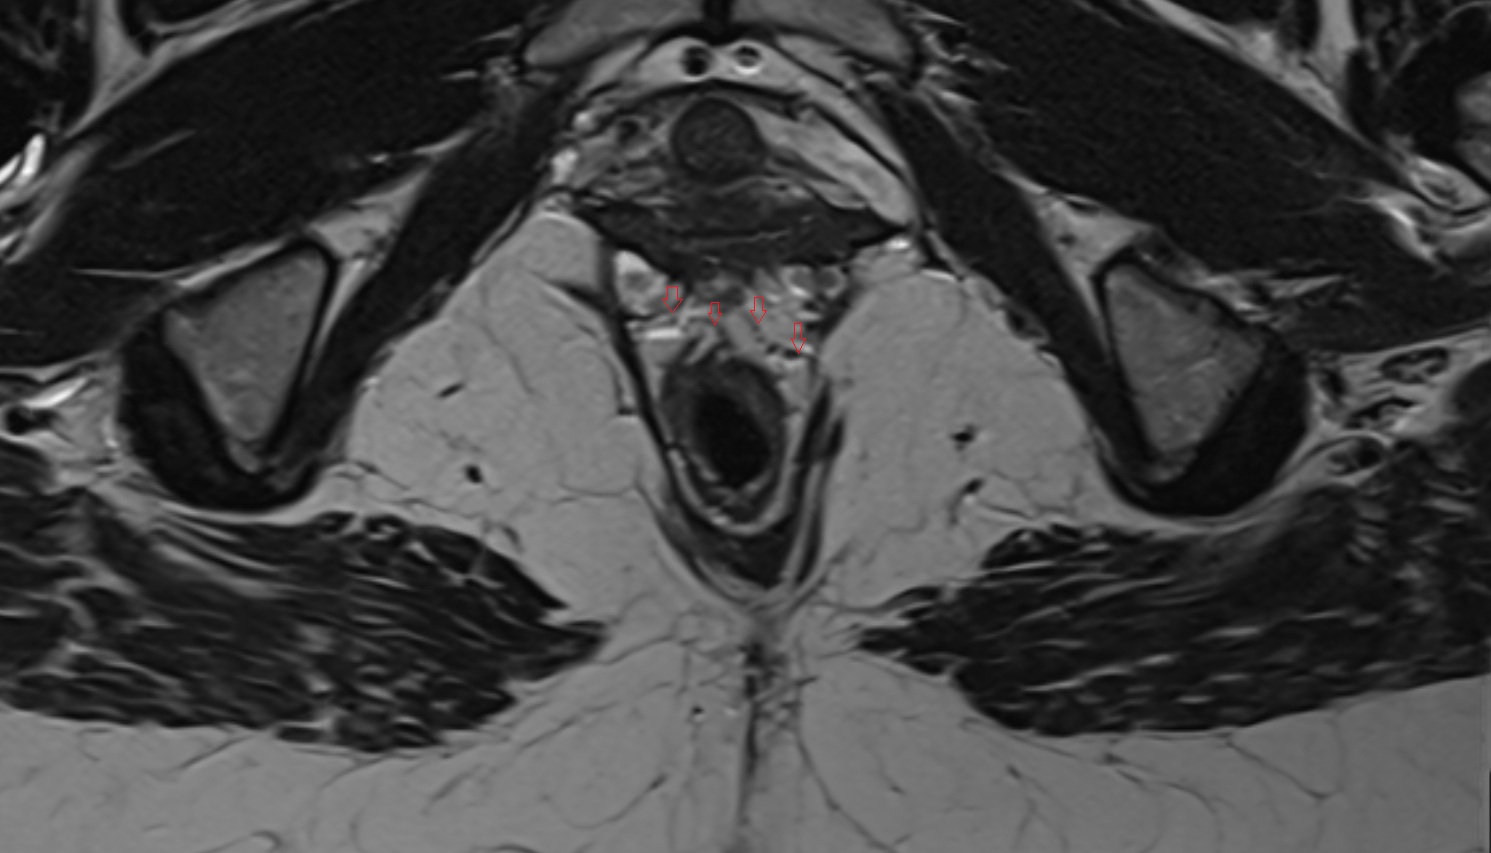

- Urinary bladder

- Uterus

- Cervix of uterus

- Vagina

- Endocervical canal

- Stroma of the cervix

- Internal os of the cervix

- External os of the cervix